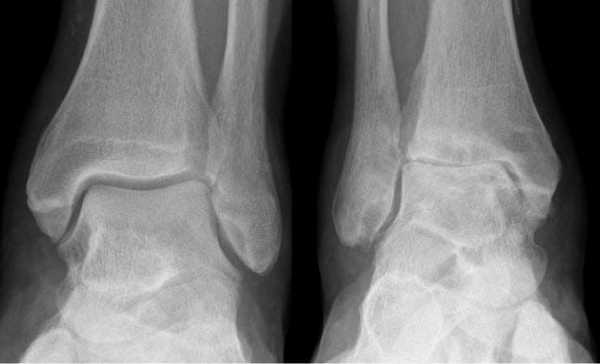

- Рентгенография с нагрузкой голеностопного сустава в прямой и боковой проекциях стопы. Рекомендуется захватывать нижние две трети голени для исключения возможных деформаций на этом уровне. В случаях грубой деформации голеностопного сустава или голени рекомендуется для сравнения выполнять рентгенографию противоположной конечности

- Тщательная оценка причин деформации голеностопного сустава: недостаточность латеральных связок или эрозии медиального отдела сустава; недостаточность дельтовидной связки или эрозиилатерального отдела сустава; неправильная консолидация большеберцовой или таранной костей

- Определение объема движений в голеностопном, подтаранном и поперечном суставах стопы. Возможна ли пассивная коррекция деформации?